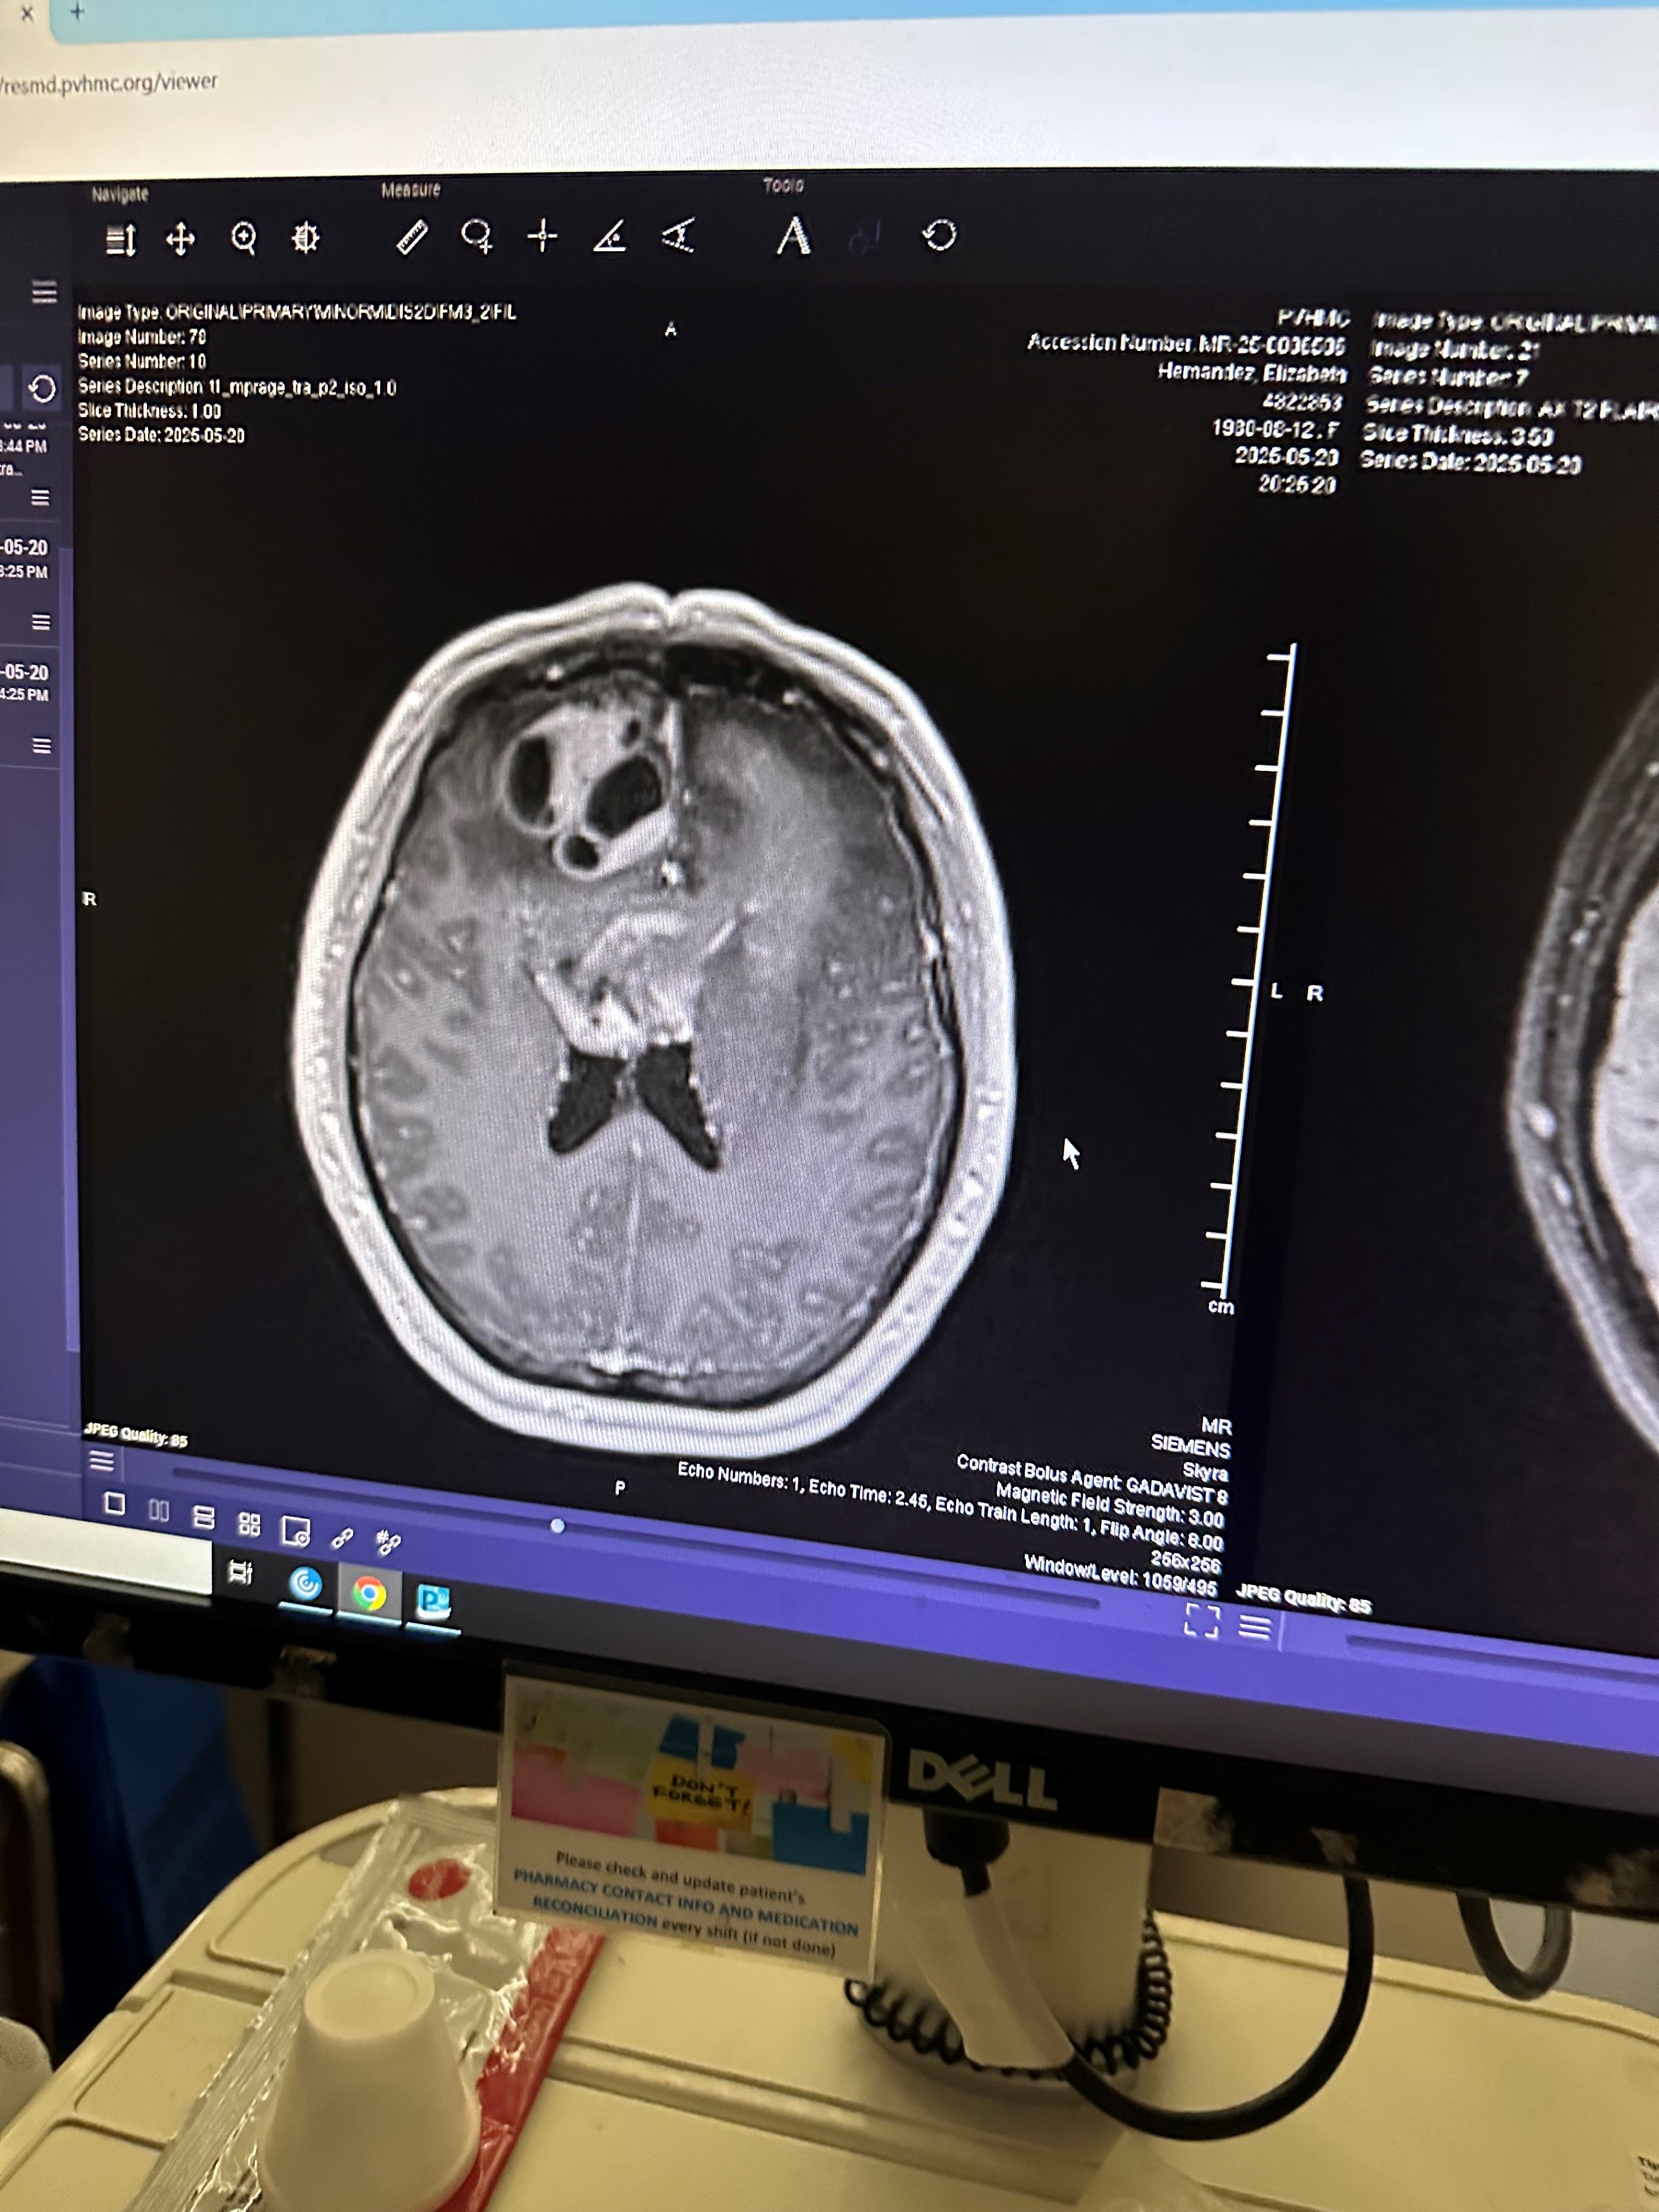

On May 21, 2025, their lives changed forever when Elizabeth was diagnosed with Glioblastoma, an aggressive form of brain cancer.

For some time, Daniel noticed troubling changes in Liz. She began to suffer from migraines, changes in behavior, and had a lack of energy. As her symptoms intensified, Daniel rushed her to Pomona Valley Hospital for answers. What they hoped might be a treatable condition turned out to be far more devastating. Tests revealed two tumors, leading to emergency surgery on Friday to remove them. Thankfully, the surgery was successful, but Elizabeth’s battle with cancer is just beginning.